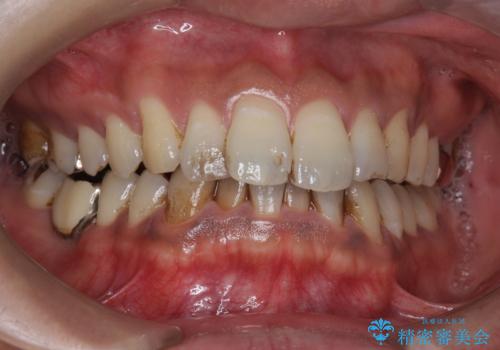

タバコによるヤニ、着色、歯の汚れをPMTC(60分コース)で除去。